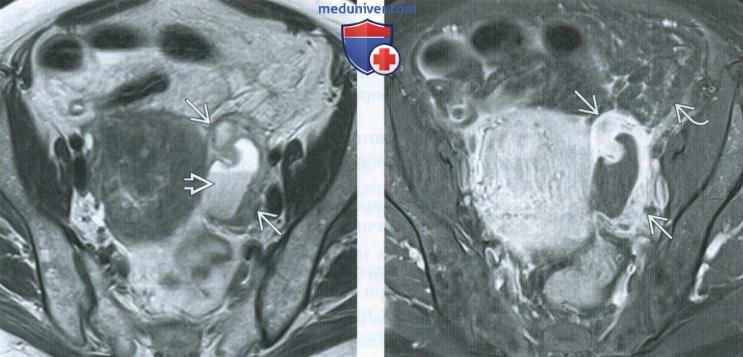

КТ-исследование абсцесса малого таза: Визуализация и диагностика

Раздел: Фотоальбом решений